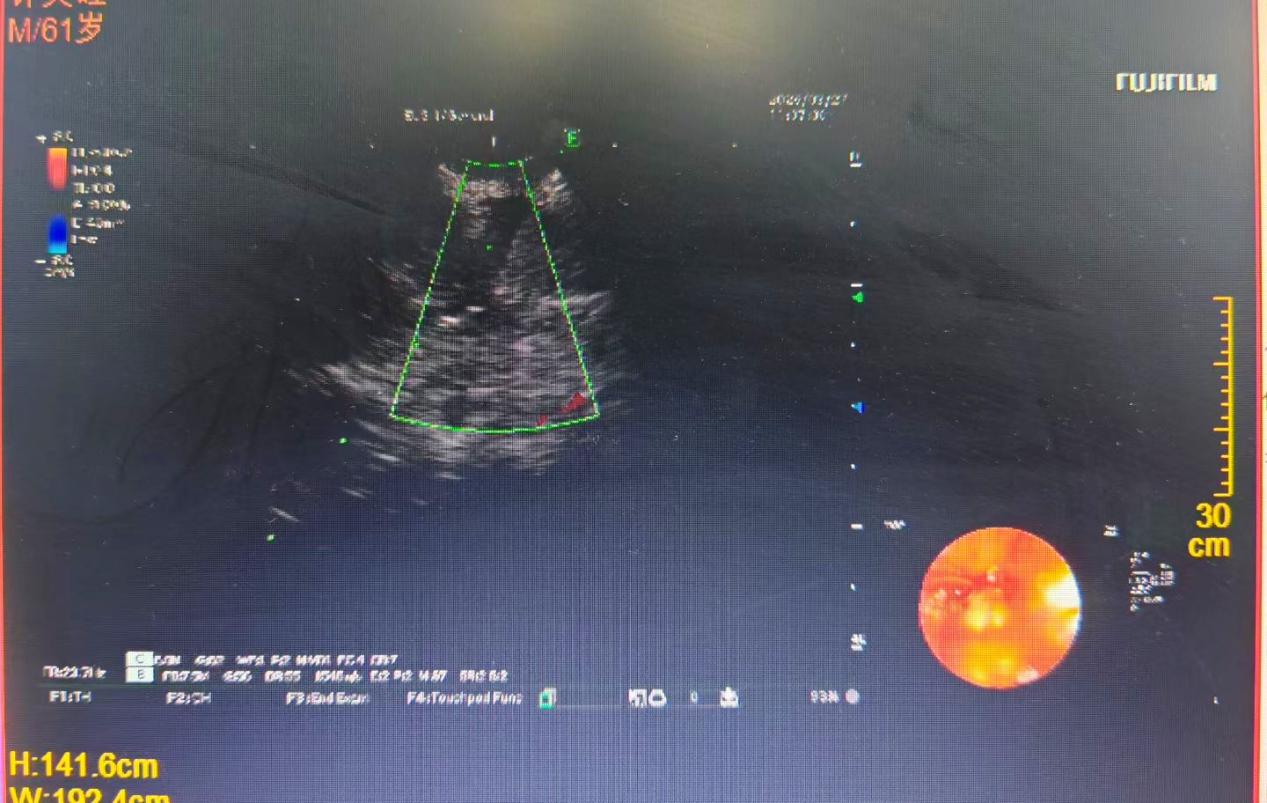

术中,团队在超声实时引导下精准定位患者右肺肿大淋巴结,苏政军主任医师精细操作,反复校准穿刺路径后,通过细针精准穿刺抽取组织,成功获取了合格的病理标本。整个手术过程中,患者生命体征平稳,术后无明显不适,恢复情况良好。待病理结果明确后,科室将第一时间为患者量身定制后续抗肿瘤治疗方案,实现精准施治。

EBUS-TBNA操作中